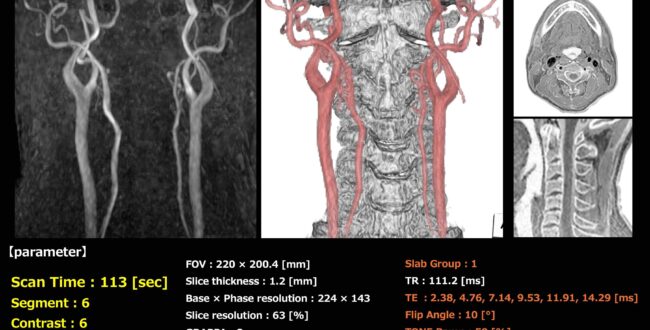

古い装置でもあきらめない!?頭頚部MRA時短撮像